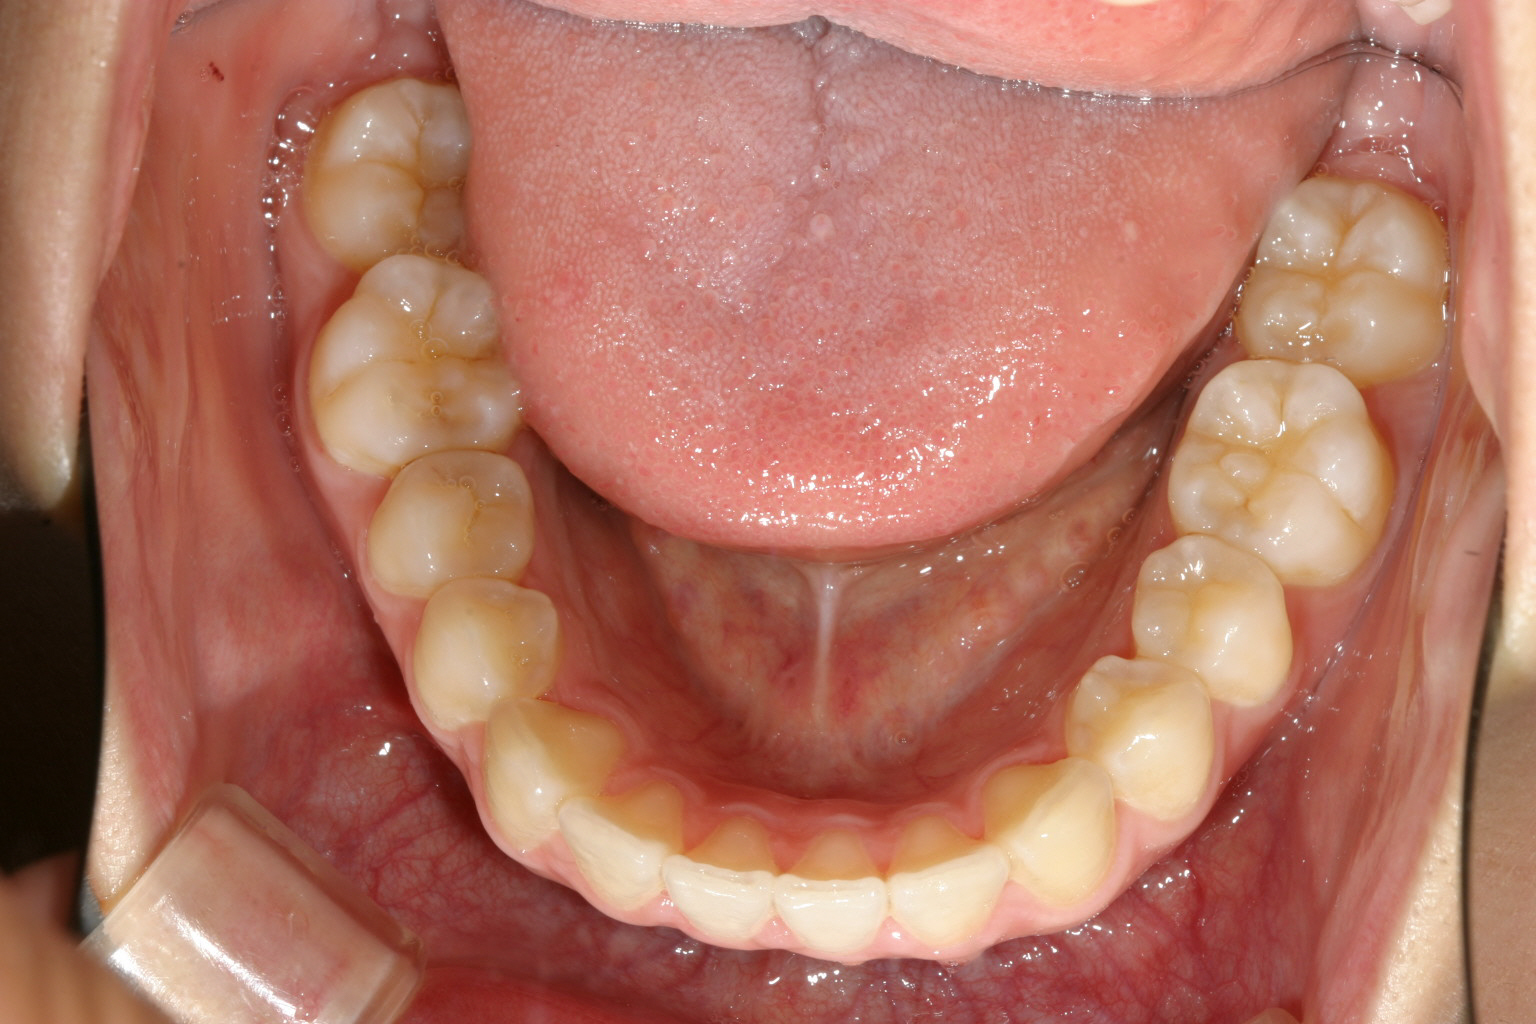

下顎は少し乱れてますがさほどでもないです。

こちらも綺麗なアーチになりました。

こちらの症例は僅かな翼状捻転だけが問題でしたからインビザラインで難なく改善しました。

これくらいの不正咬合でワイヤーはちょっとと思われる方はインビザラインで治療されればこれ位短期間で十分改善出来ると言ういいケースです。